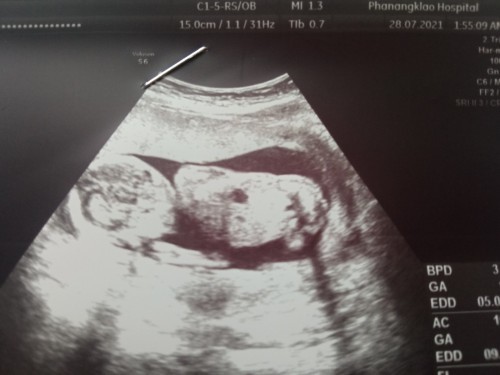

อัลตร้าซาวด์

อัลตร้าซาวด์นี่ทราบเพศ100%ไหมคะ เมื่อ10ปีก่อนเคยมีประสบการณ์ที่หมอบอกว่าได้เพศชาย แต่คลอดออกมาได้เพศหญิง เลยสงสัยค่ะ#ขอบคุณสำหรับคำตอบค่ะ #ใครมีประสบการณ์

การอัลตร้าซาวด์ไม่สามารถบอกเพศ และ ความผิดปกติได้ 100% นะคะ หากอยากทราบเพศ 100% ตรวจนิฟค่ะ เพราะเขาจะดูจากโครโมโซมเด็กว่าเป็นเพศอะไร เเละ ดูได้ถึงความผิดปกติบางอย่างได้ชัดเจนค่ะ

ไม่มีคำว่า 100% นะคะ นอกจากน้องจะอ้าขาให้เห็นชัดๆแล้วขึ้นอยู่กับเครื่องอัลตร้าซาวด์ของหมอที่ใช้ด้วยค่ะว่าชัดหรือเปล่า

ไม่มีอะไร 100% ค่ะ หมอก็บอกได้เท่าที่เห็น และน่าจะเป็นค่ะ 😊

ขึ้นอยู่กับว่าเห็นเพศน้องชัดหรือเปล่าค่ะ